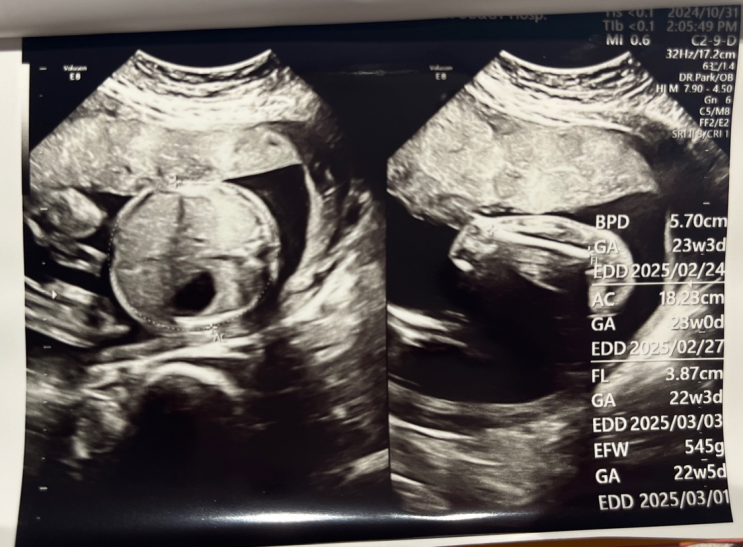

[임신일기] 떨리는 21주차 정밀초음파 검사 (21주 2~3일)

1,2차 기형아 검사에서 한번의 이벤트가 있어서 정밀초음파 하는 날이 너무 떨렸다. 제발 무사히 넘어가길 ...